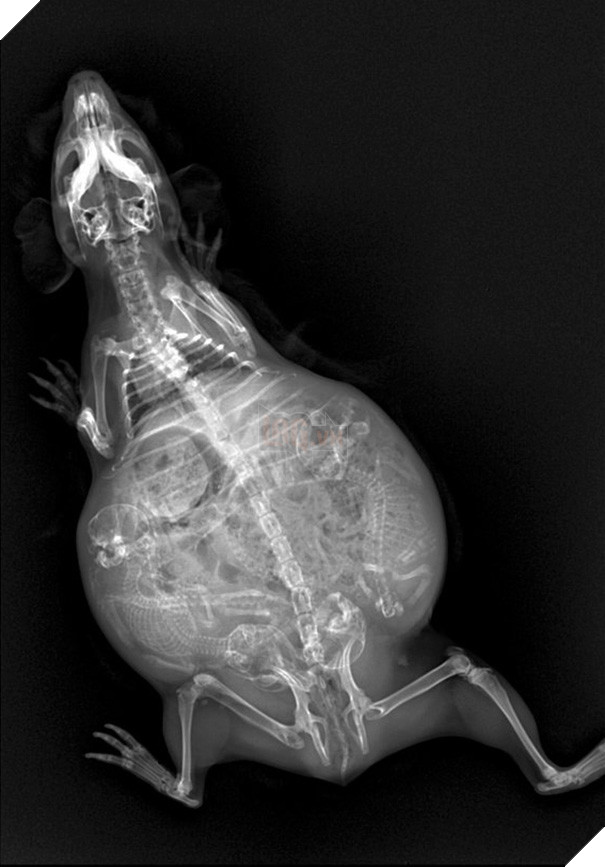

Ảnh chụp X-quang một con chuột lang đang mang thai.